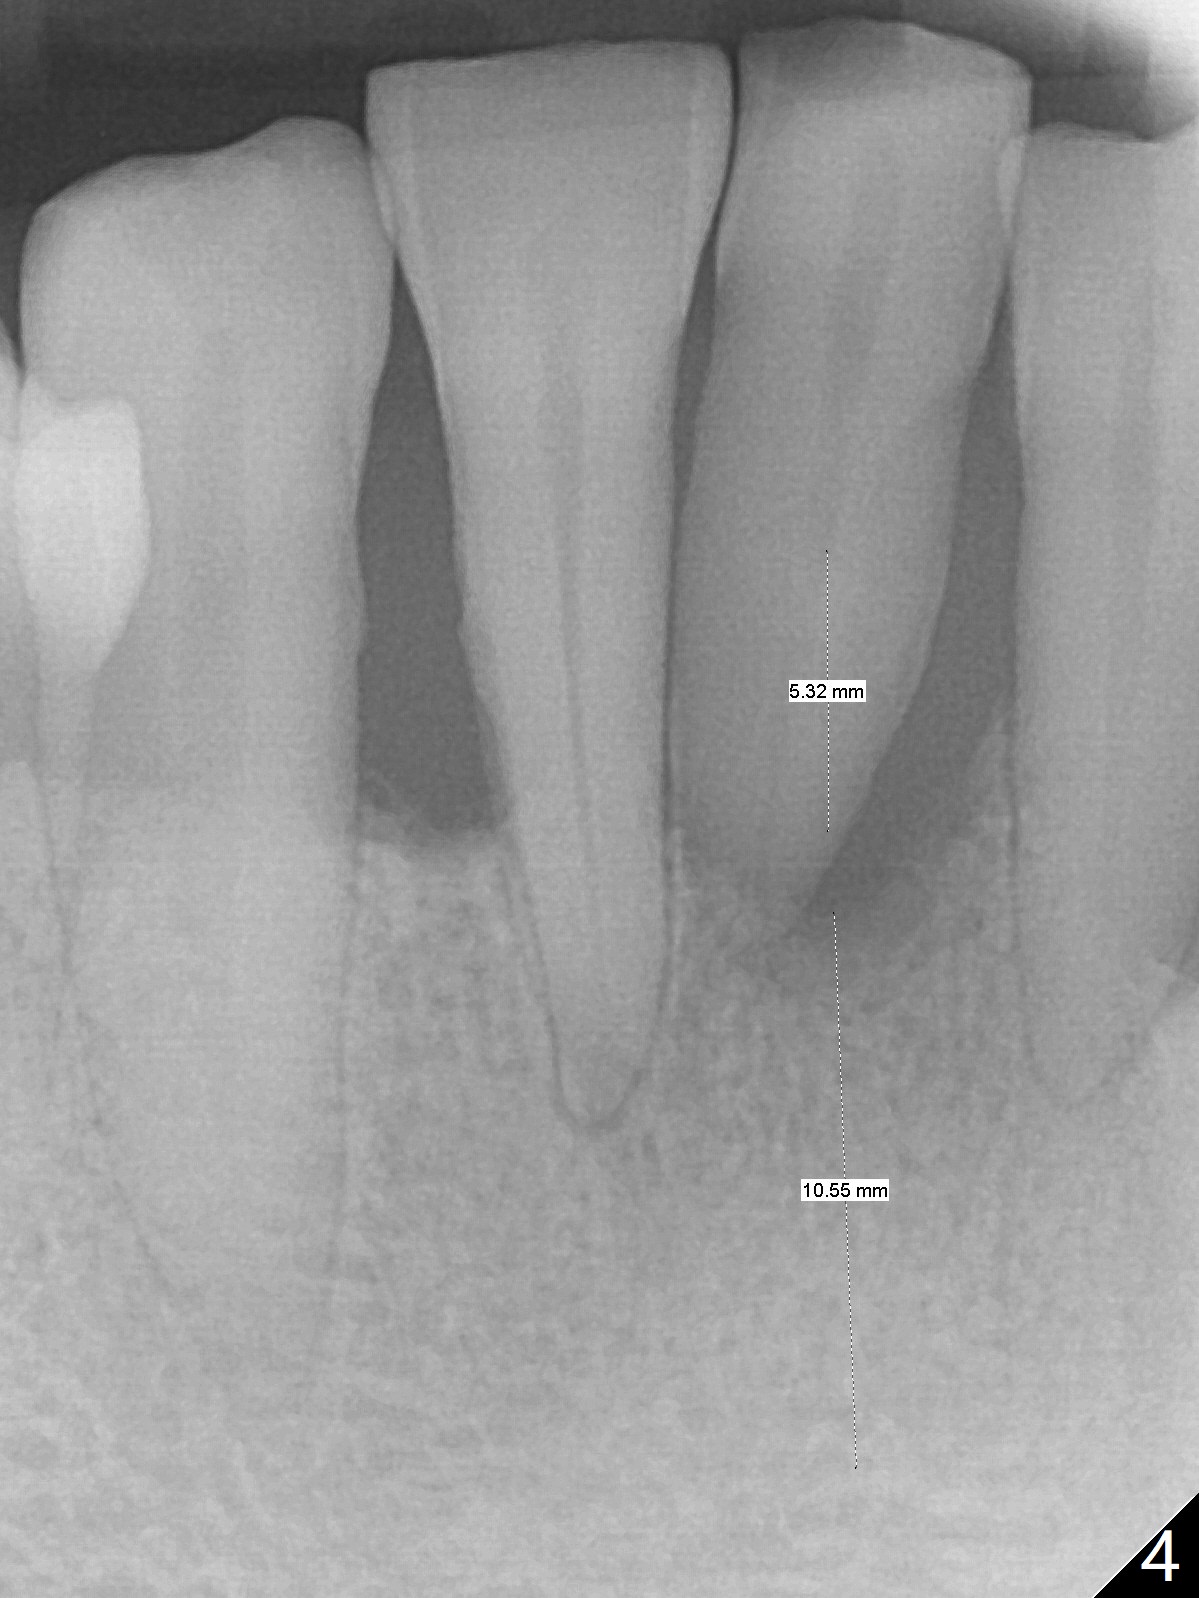

There is gingival inflammation at #25 buccally (Fig.1) and lingually (Fig.2). The bone loss is severe (Fig.3). Soft and hard tissue heights are 5 mm (cuff will be 4 mm) and 10 mm (implant will be 12 mm with 2 mm outside the native bone, Fig.4). The apex of the affected tooth appears deviated distal (Fig.5 *). The initial osteotomy happens to follow the long axis of the socket (Fig.6); to establish a correct trajectory, a new osteotomy should be made at the site labeled as a red line. In fact it is executed as planned (Fig.7). Because of the narrow flat ridge buccolingually, a 2.5x12(4) mm 1-piece implant is placed with >40 Ncm (Fig.8). With deeper placement of the implant, Vanilla graft is placed in 2 steps (Fig.9,10). The patient will return 2.5 months for extraction and implant of the fused teeth #22 and 23. No implant threads are exposed 10 months postop (Fig.11). CT taken 11 months postop shows that the 2.5 mm implant is in the middle of the bone (Fig.12) or 2 years post cementation (Fig.13).